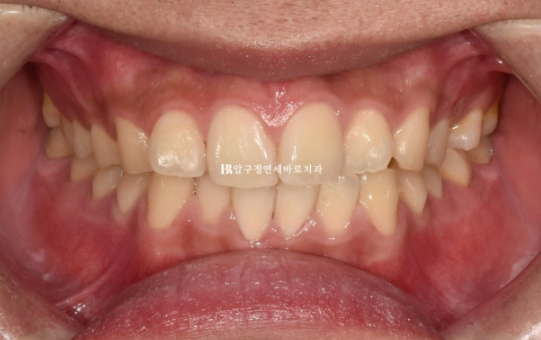

23.12

1년 전 인비절라인 교정을 위해 내원하신 환자분입니다.

삐뚤한 앞니가 보입니다.

파란 화살표 어금니는 아래 어금니와 거꾸로 물리는 반대교합 입니다.

정밀진단 결과 배열개선, 반대교합 개선 등을 목표로 인비절라인 라이트를 권유드렸습니다,